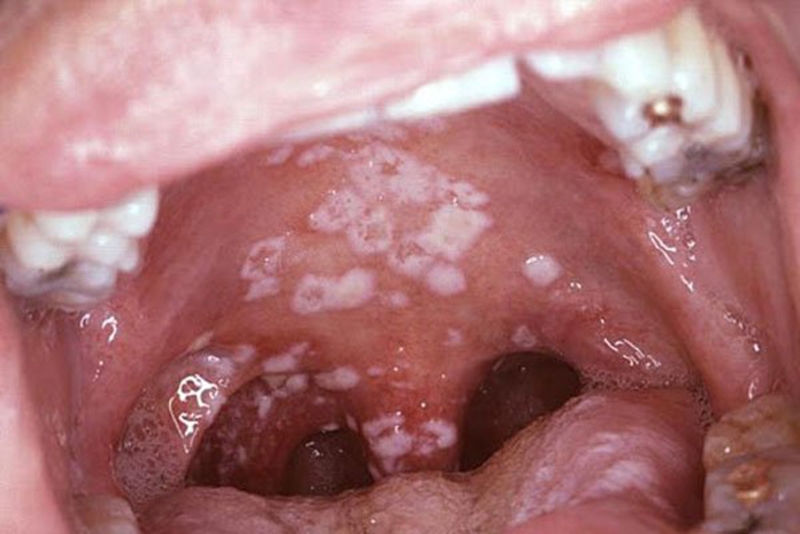

Nấm họng Candida là bệnh do nấm Candida Albicans gây nên. Khi đó, nấm sẽ xuất hiện nhiều trên niêm mạc miệng và cổ họng. Nấm Candida albicans là loại nấm phổ biến, sống cộng sinh trên da và bên trong cơ thể. Ở khu vực cổ họng, nếu không được vệ sinh sạch sẽ sẽ tạo môi trường lý tưởng cho nấm sinh sôi, phát triển.

Các vết thương do loại nấm này gây ra có màu trắng kem. Dấu hiệu ban đầu đau nhức và ngứa rát vùng tổn thương, gây ảnh hưởng tới các hoạt động ăn uống, sinh hoạt.

Những thông tin cần biết về nấm họng Candida 1 Nấm họng Candida

• Má trong, lưỡi, vòm họng và cổ họng xuất hiện nhiều tổn thương màu đốm trắng kem.